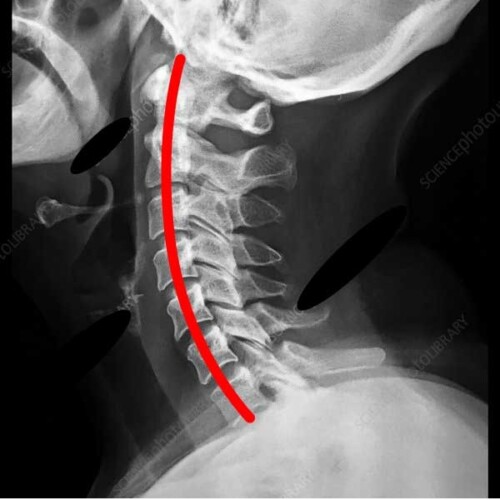

正常な頚椎

ストレートネック

普段から頭部が前方に出た姿勢を長時間取る事で頚椎の自然なカーブが無くなり、首の筋肉や椎間板にストレスがかかるようになります。

その結果肩こりが起こりやすくなり、酷くなると手の痺れや頚椎ヘルニアに移行する事があります。